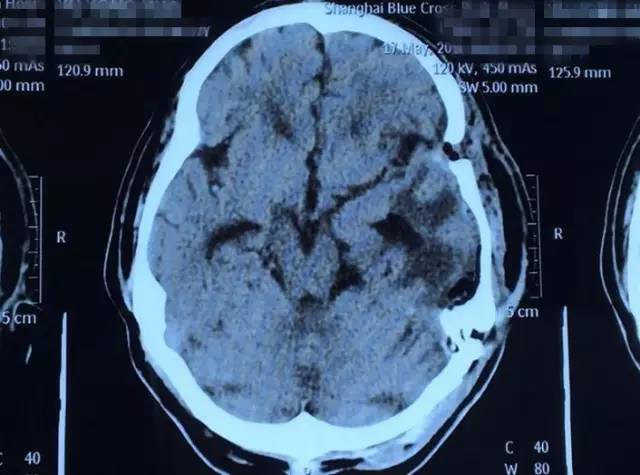

术后影像资料:白色肿瘤物消失

4月23日上午8:00,一切术前准备工作完毕后,虞文军在我院DSA血管介入诊疗科接受了“超选择性全脑血管造影术+脑膜瘤供血动脉栓塞术”,对肿瘤供血动脉进行了栓塞。接着,虞文军被推入了手术室,在全麻状态下,潘仁龙主任为其实施了“左侧颞底部巨大脑膜瘤切除术”。去除骨瓣后,患者颅内压极高,见硬膜肿瘤已侵蚀,肿瘤组织质较韧,呈砂砾状。为进一步减少术中出血,将周边组织悬吊好后,薄膜内分块切除肿瘤组织、分离肿瘤包膜,肿瘤被大部切除后,上手术显微镜处理中颅离底肿瘤基底部并电烧基底面,肿瘤组织被全部切除。手术完满结束,术中出血约600ml,术后患者安返ICU重症监护室进行监护。

下午约6:30,走出手术室的那一刻,所有人长长地舒了一口气,沈建康教授更是意味深长地说:“我10年都没见过这么大的脑肿瘤了......”据悉,术后患者随即恢复清醒,自我感觉头脑较前更清醒,语音、语速恢复较好,不到半个月便已能正常行走,无不适,5月25日顺利出院。